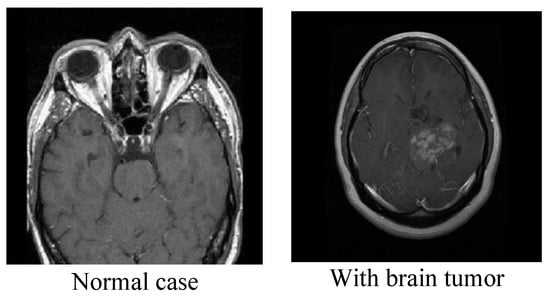

3.1. The First Dataset

3.2. The Second Dataset